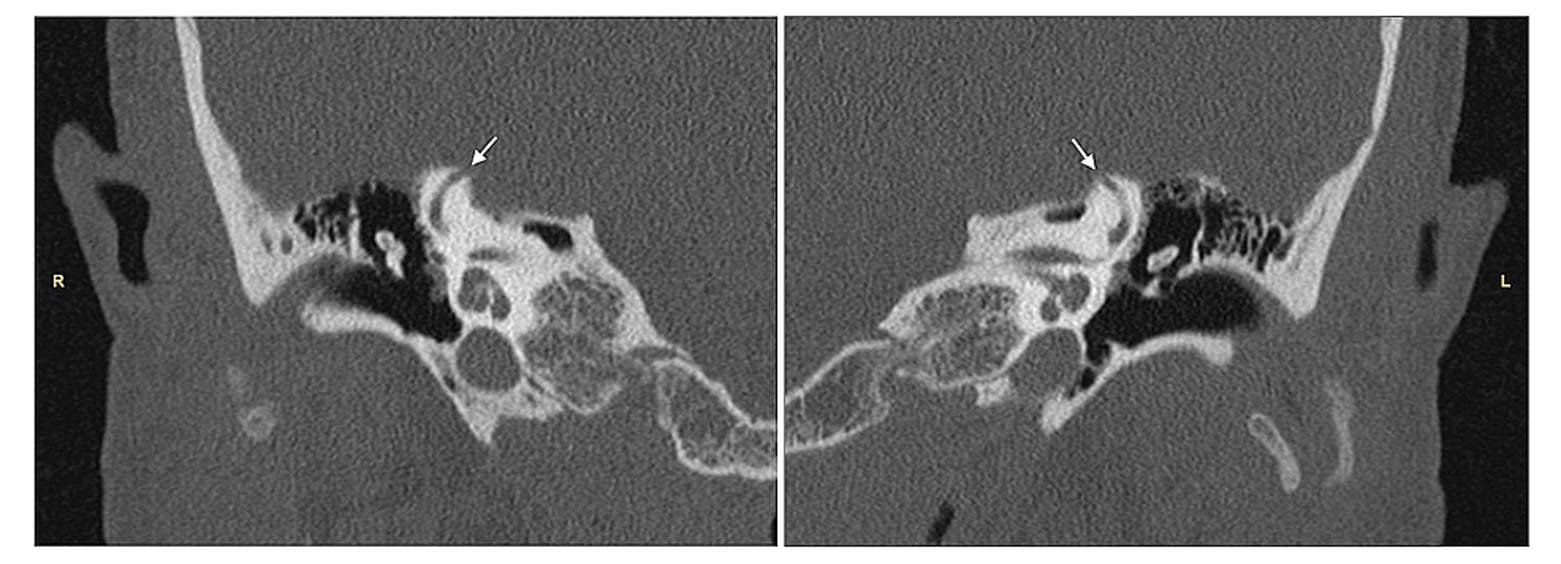

Die Dehiszenz des oberen Bogenganges (Superior Semicircular Canal Dehiscence, SSCD) ist eine Erkrankung, die durch eine Ausdünnung oder Öffnung des Knochens am oberen Ende des oberen Bogenganges im Innenohr gekennzeichnet ist.

Superior Bogengangsdehiszenz (SSCD) ist eine Erkrankung, die durch eine Ausdünnung oder Öffnung der Knochenschicht oberhalb des superioren Bogengangs im Innenohr gekennzeichnet ist. Diese Anomalie kann das Hör- und Gleichgewichtssystem beeinträchtigen.